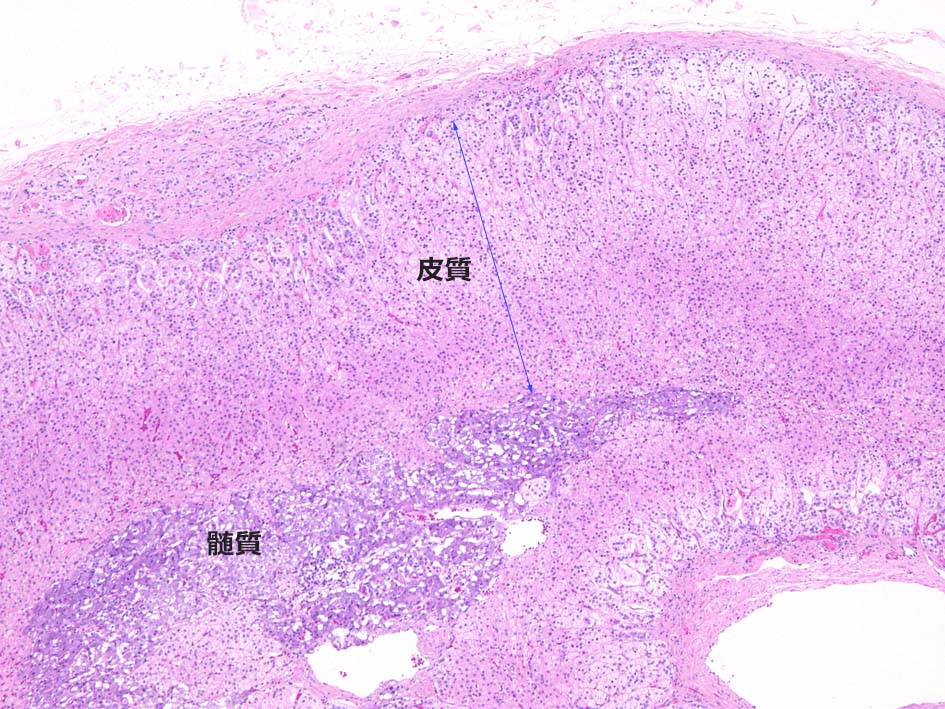

副腎は細胞成分に乏しい線維性被膜に被覆される. 被膜下には皮質の層構造が認められ中心部には交感神経由来細胞が集簇し髄質を形成している.

皮質には境界の不明瞭な3層構造が認められる. 被膜直下より, 球状層(Zona Glomerulosa), 束状層(Zona Fasciculata), 網状層(Zona Reticularis)と呼ばれ各々性状, 形態の異なる細胞より構成されている.

髄質ではアドレナリン, ノルアドレナリンなどのカテコラミンを合成分泌している. 「褐色細胞」または「クロム親和性細胞」と呼ばれる中心性類円形核と好塩基性(ヘマトキシリン好性)細胞質をもつ分泌細胞が索をつくり, 索の間には毛細血管を含む細い線維性結合組織が介在している.

神経節細胞が不規則に分泌細胞間に点在している. 神経節細胞内には時に好酸性球形の小体を含むことがある. 皮質細胞の小集塊が髄質内に散見されることがある他, 分泌細胞間にS-100陽性のsustentaclar cellsが介在する.HEでの同定は難しい.